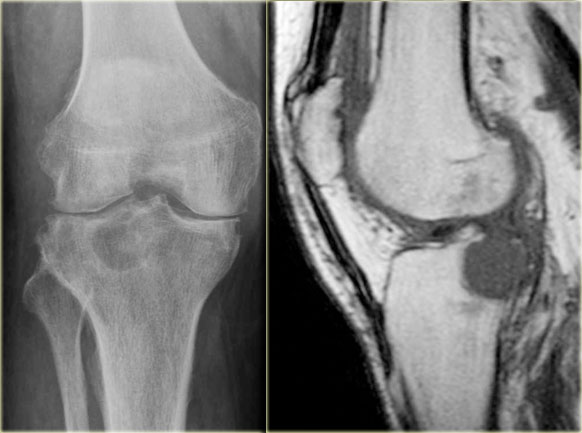

Giant cell tumor (2)

On the left a giant cell tumor presenting as an eccentric lytic lesion in the medial epi- and metaphysis of the distal femur.

There is a small transitional zone resulting in well-defined borders.

Continue with the MR-images.

Giant cell tumor (2) continued

MR-images of the same patient.

Sagittal T1-weighted TSE images before and after Gd.

The tumor extends to the subchondral bone plate with endosteal cortical involvement.

There is inhomogeneous enhancement.

On T2-weighted image, the tumor has a remarkable low SI, which is commonly seen in GCT.

There is surrounding edema with high SI.